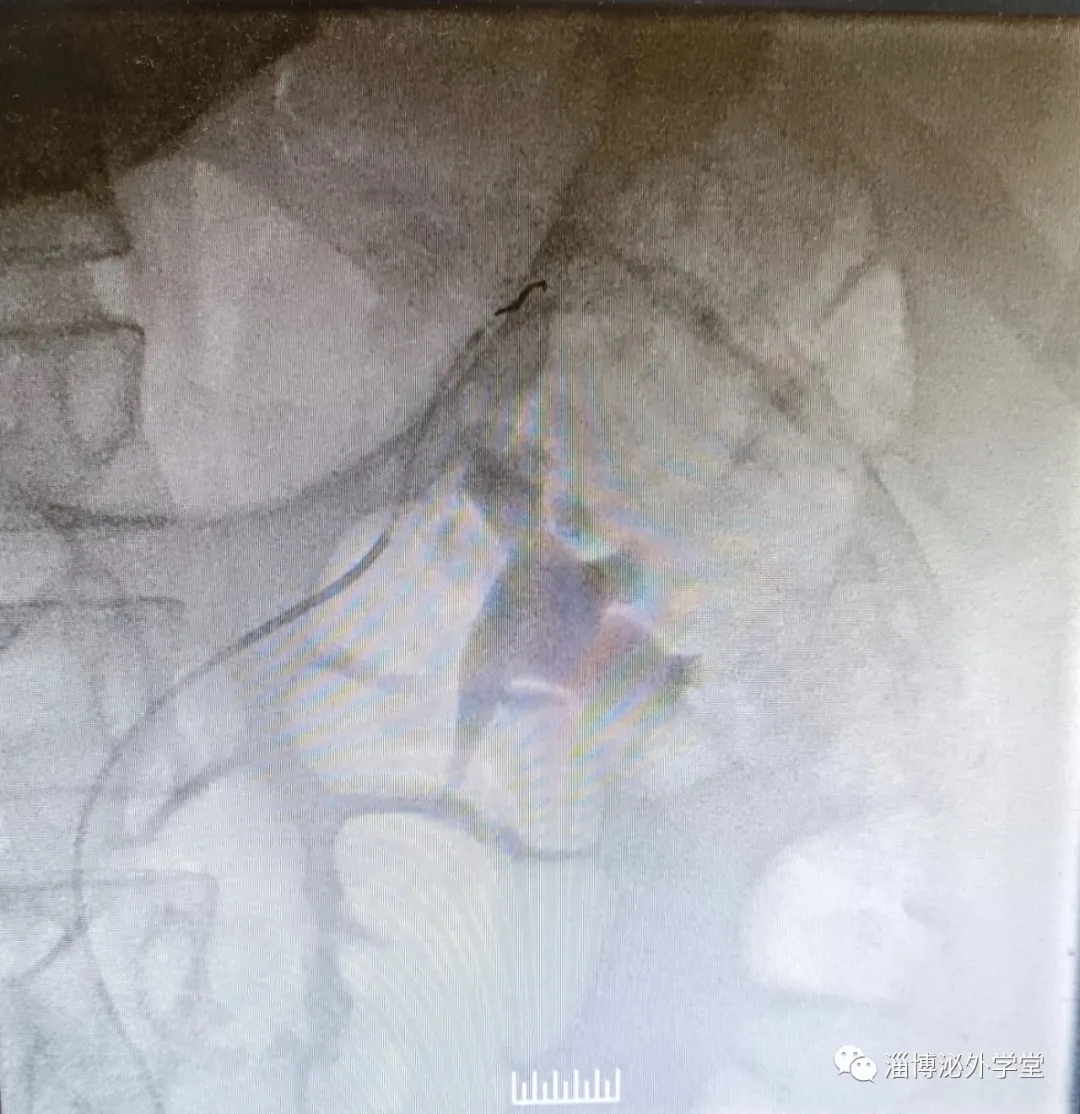

經(jīng)過完善的術(shù)前準(zhǔn)備,患者被送入介入手術(shù)室,由劉綿春親自行介入手術(shù),在C型臂的引導(dǎo)下,經(jīng)皮股動脈穿刺插管,通過多次選擇性血管造影,發(fā)現(xiàn)患者腎被膜下有2條小血管破裂出血,并仍然在往外溢血,立即給予局部栓塞止血,最終患者腎內(nèi)出血點(diǎn)被全部控制,左腎組織得以保留。

術(shù)后,聶清生主任與劉綿春分析患者病情,一致認(rèn)為腎損傷的治療原則是徹底止血,最大限度地保留有功能的腎臟和改善全身狀況。而以往對腎挫裂傷患者所采用的腎切除術(shù)對患者損傷大,且切除患腎后留下孤立腎,一旦發(fā)生病變或損傷就沒有多余的腎組織代替(除了換腎),有多種潛在危險。此次泌尿外科與血管介入科默契合作,造?;颊叩耐瑫r,醫(yī)院腎挫裂傷的治療也得到了新的進(jìn)展,運(yùn)用超選擇血管栓塞術(shù)控制出血,一次性栓塞止血成功。